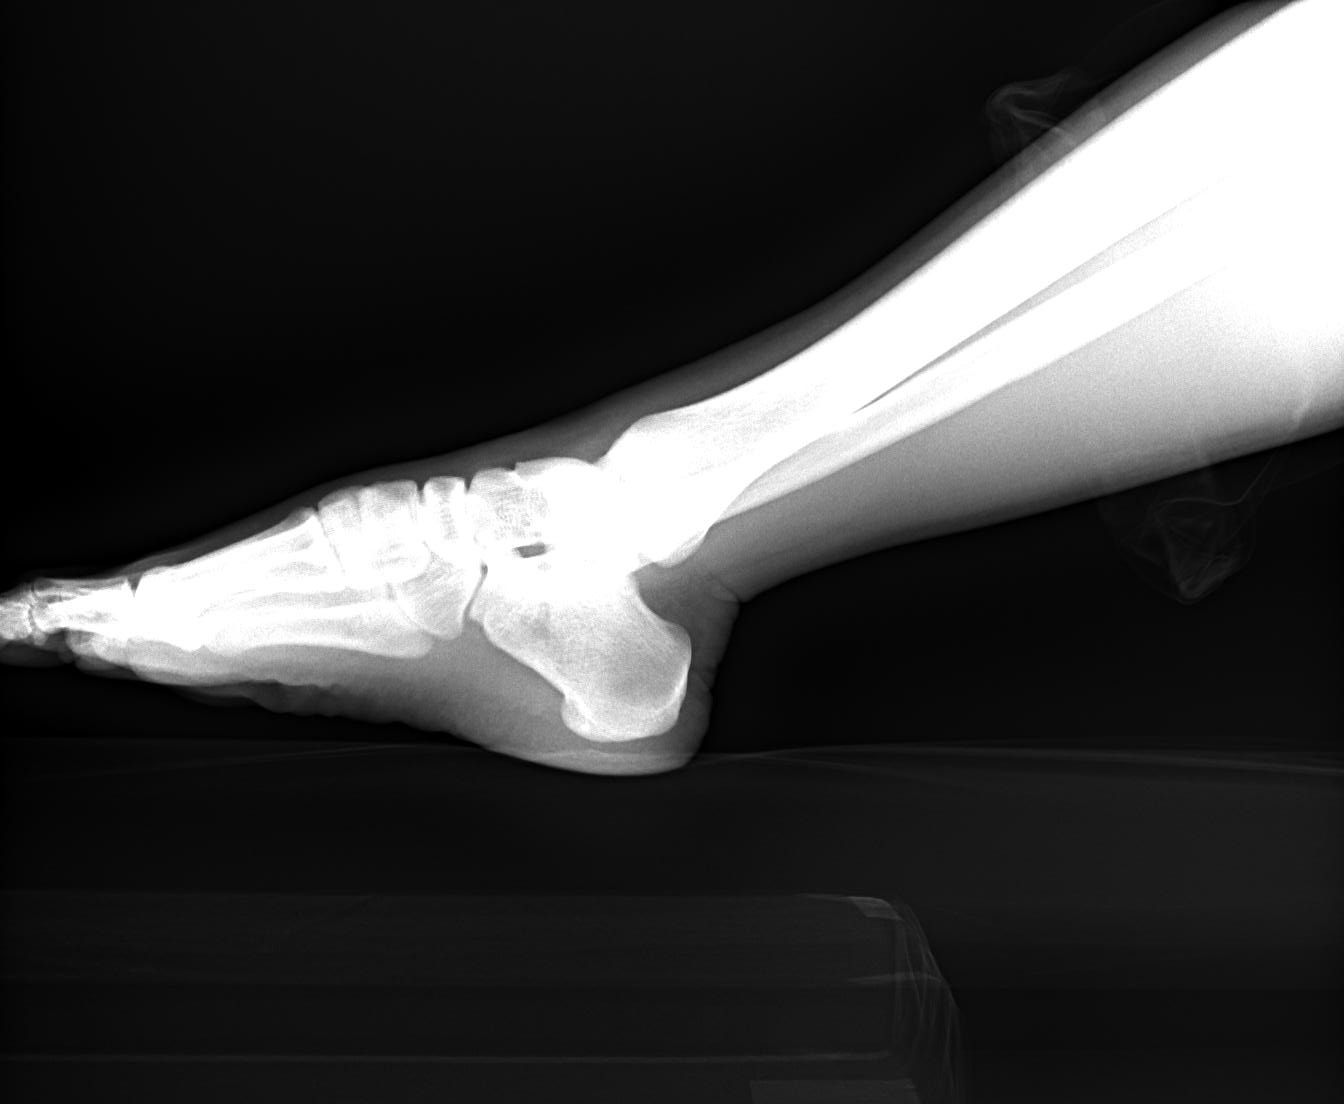

Hallux Rigidus & Anterior Shin Splint Syndrome

Hallux Rigidus is a kind of osteoarthritis of the 1st MP joint of the big toe. In this condition 1st, MP joint ROM is limited and painful. Due to ROM limitation, movement of the ankle joint is increased, and it ...